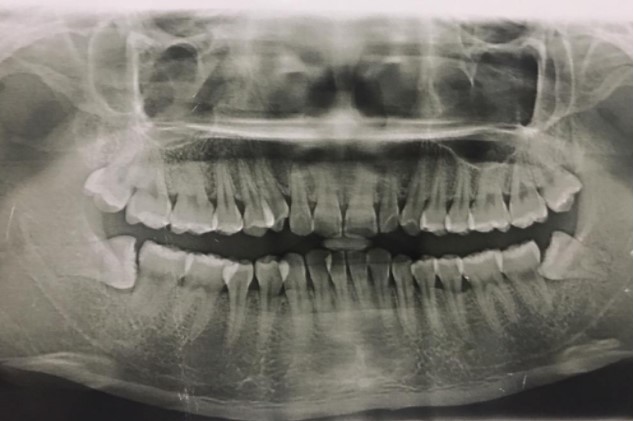

1、患者,男,38歲。上前牙變色1年,自述上前牙5年前受過外傷,唇側(cè)傾斜,檢查可見左上1牙冠變色,牙冠缺損近1/2,牙髓測(cè)試無(wú)反應(yīng),X線根尖片顯示患牙無(wú)明顯異常,全景片顯示雙側(cè)下頜智齒近中阻生,之前有發(fā)炎化膿病史,目前無(wú)咀嚼不適??谇黄溆酂o(wú)異常。

檢查情況及X線片見下圖:

(1)主訴診斷:左上1牙髓壞死(外傷)

(2)非主訴診斷:雙側(cè)下頜智齒冠周炎(近中阻生)